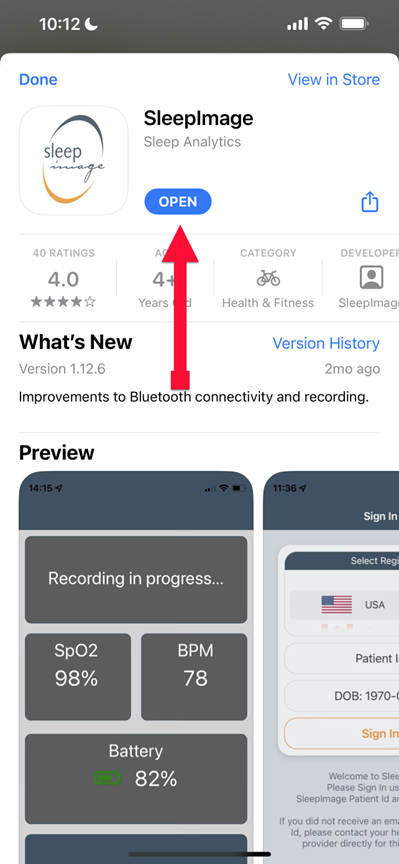

SLEEPIMAGE APP (iPhone)

SLEEPIMAGE APP (iPhone)

SLEEPIMAGE APP (iPhone)

SLEEPIMAGE APP (iPhone)

SLEEPIMAGE APP (iPhone)

SLEEPIMAGE APP (iPhone)

SLEEPIMAGE APP (iPhone)

SLEEPIMAGE APP (iPhone)

SLEEPIMAGE APP (iPhone)

SLEEPIMAGE APP (iPhone)

SLEEPIMAGE APP (iPhone)

SLEEPIMAGE APP (iPhone)

SLEEPIMAGE APP (iPhone)

SLEEPIMAGE APP (iPhone)

SLEEPIMAGE APP (iPhone)

SLEEPIMAGE APP (iPhone)

SLEEPIMAGE APP (iPhone)

SLEEPIMAGE APP (iPhone)

SLEEPIMAGE APP (iPhone)

SLEEPIMAGE APP (iPhone)

SLEEPIMAGE APP (iPhone)

SLEEPIMAGE APP (iPhone)

SLEEPIMAGE APP (iPhone)

SLEEPIMAGE APP (iPhone)

SLEEPIMAGE APP (iPhone)

SLEEPIMAGE APP (iPhone)